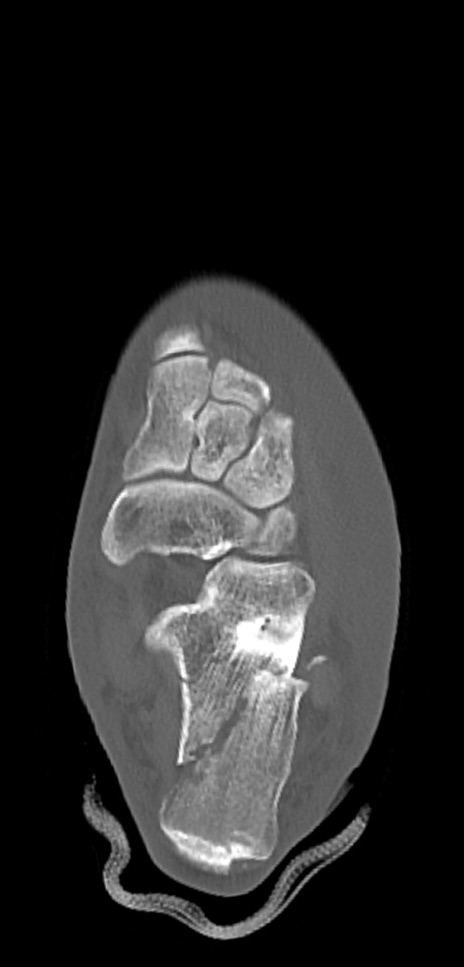

症例37 左足関節CT(横断像)

左足関節CT